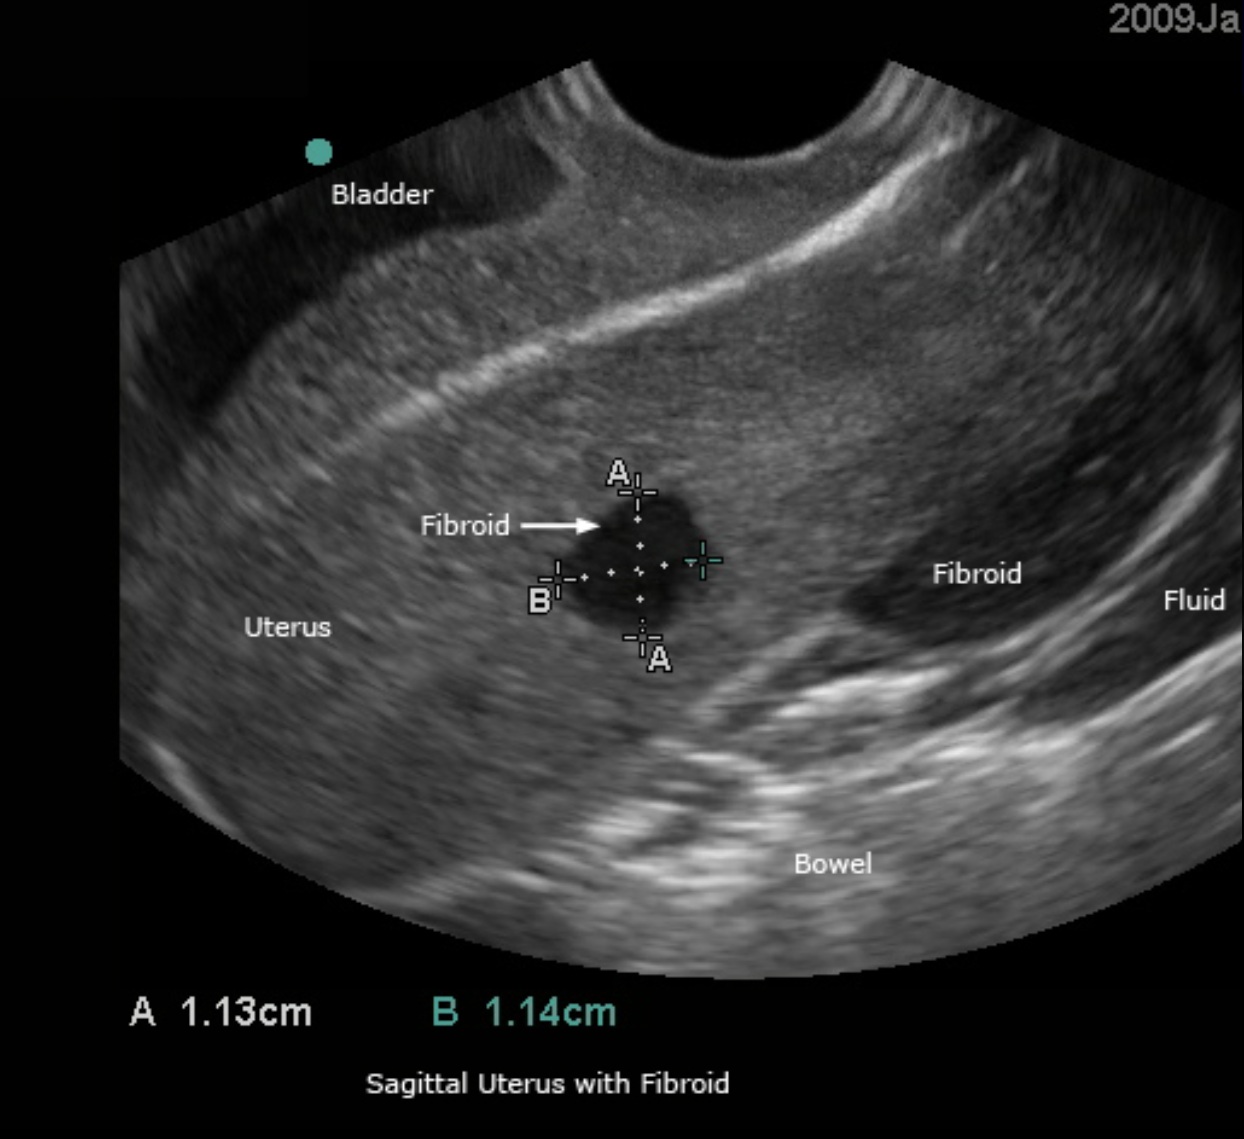

Permite visualizar la vagina, el cérvix, la vejiga y la pared vesical, el endometrio engrosado, múltiples fibromas uterinos, la acumulación de líquido en la bolsa rectal uterina, los ovarios y folículos izquierdo y derecho, los quistes ováricos, las masas/abscesos ováricos, el ligamento ancho uterino, el recto, el colon y otras estructuras asociadas.

Los fibromas uterinos presentan diversos diámetros y diferentes apariencias en las imágenes ecográficas, lo que permite entrenar en la descripción de su ubicación y medición.